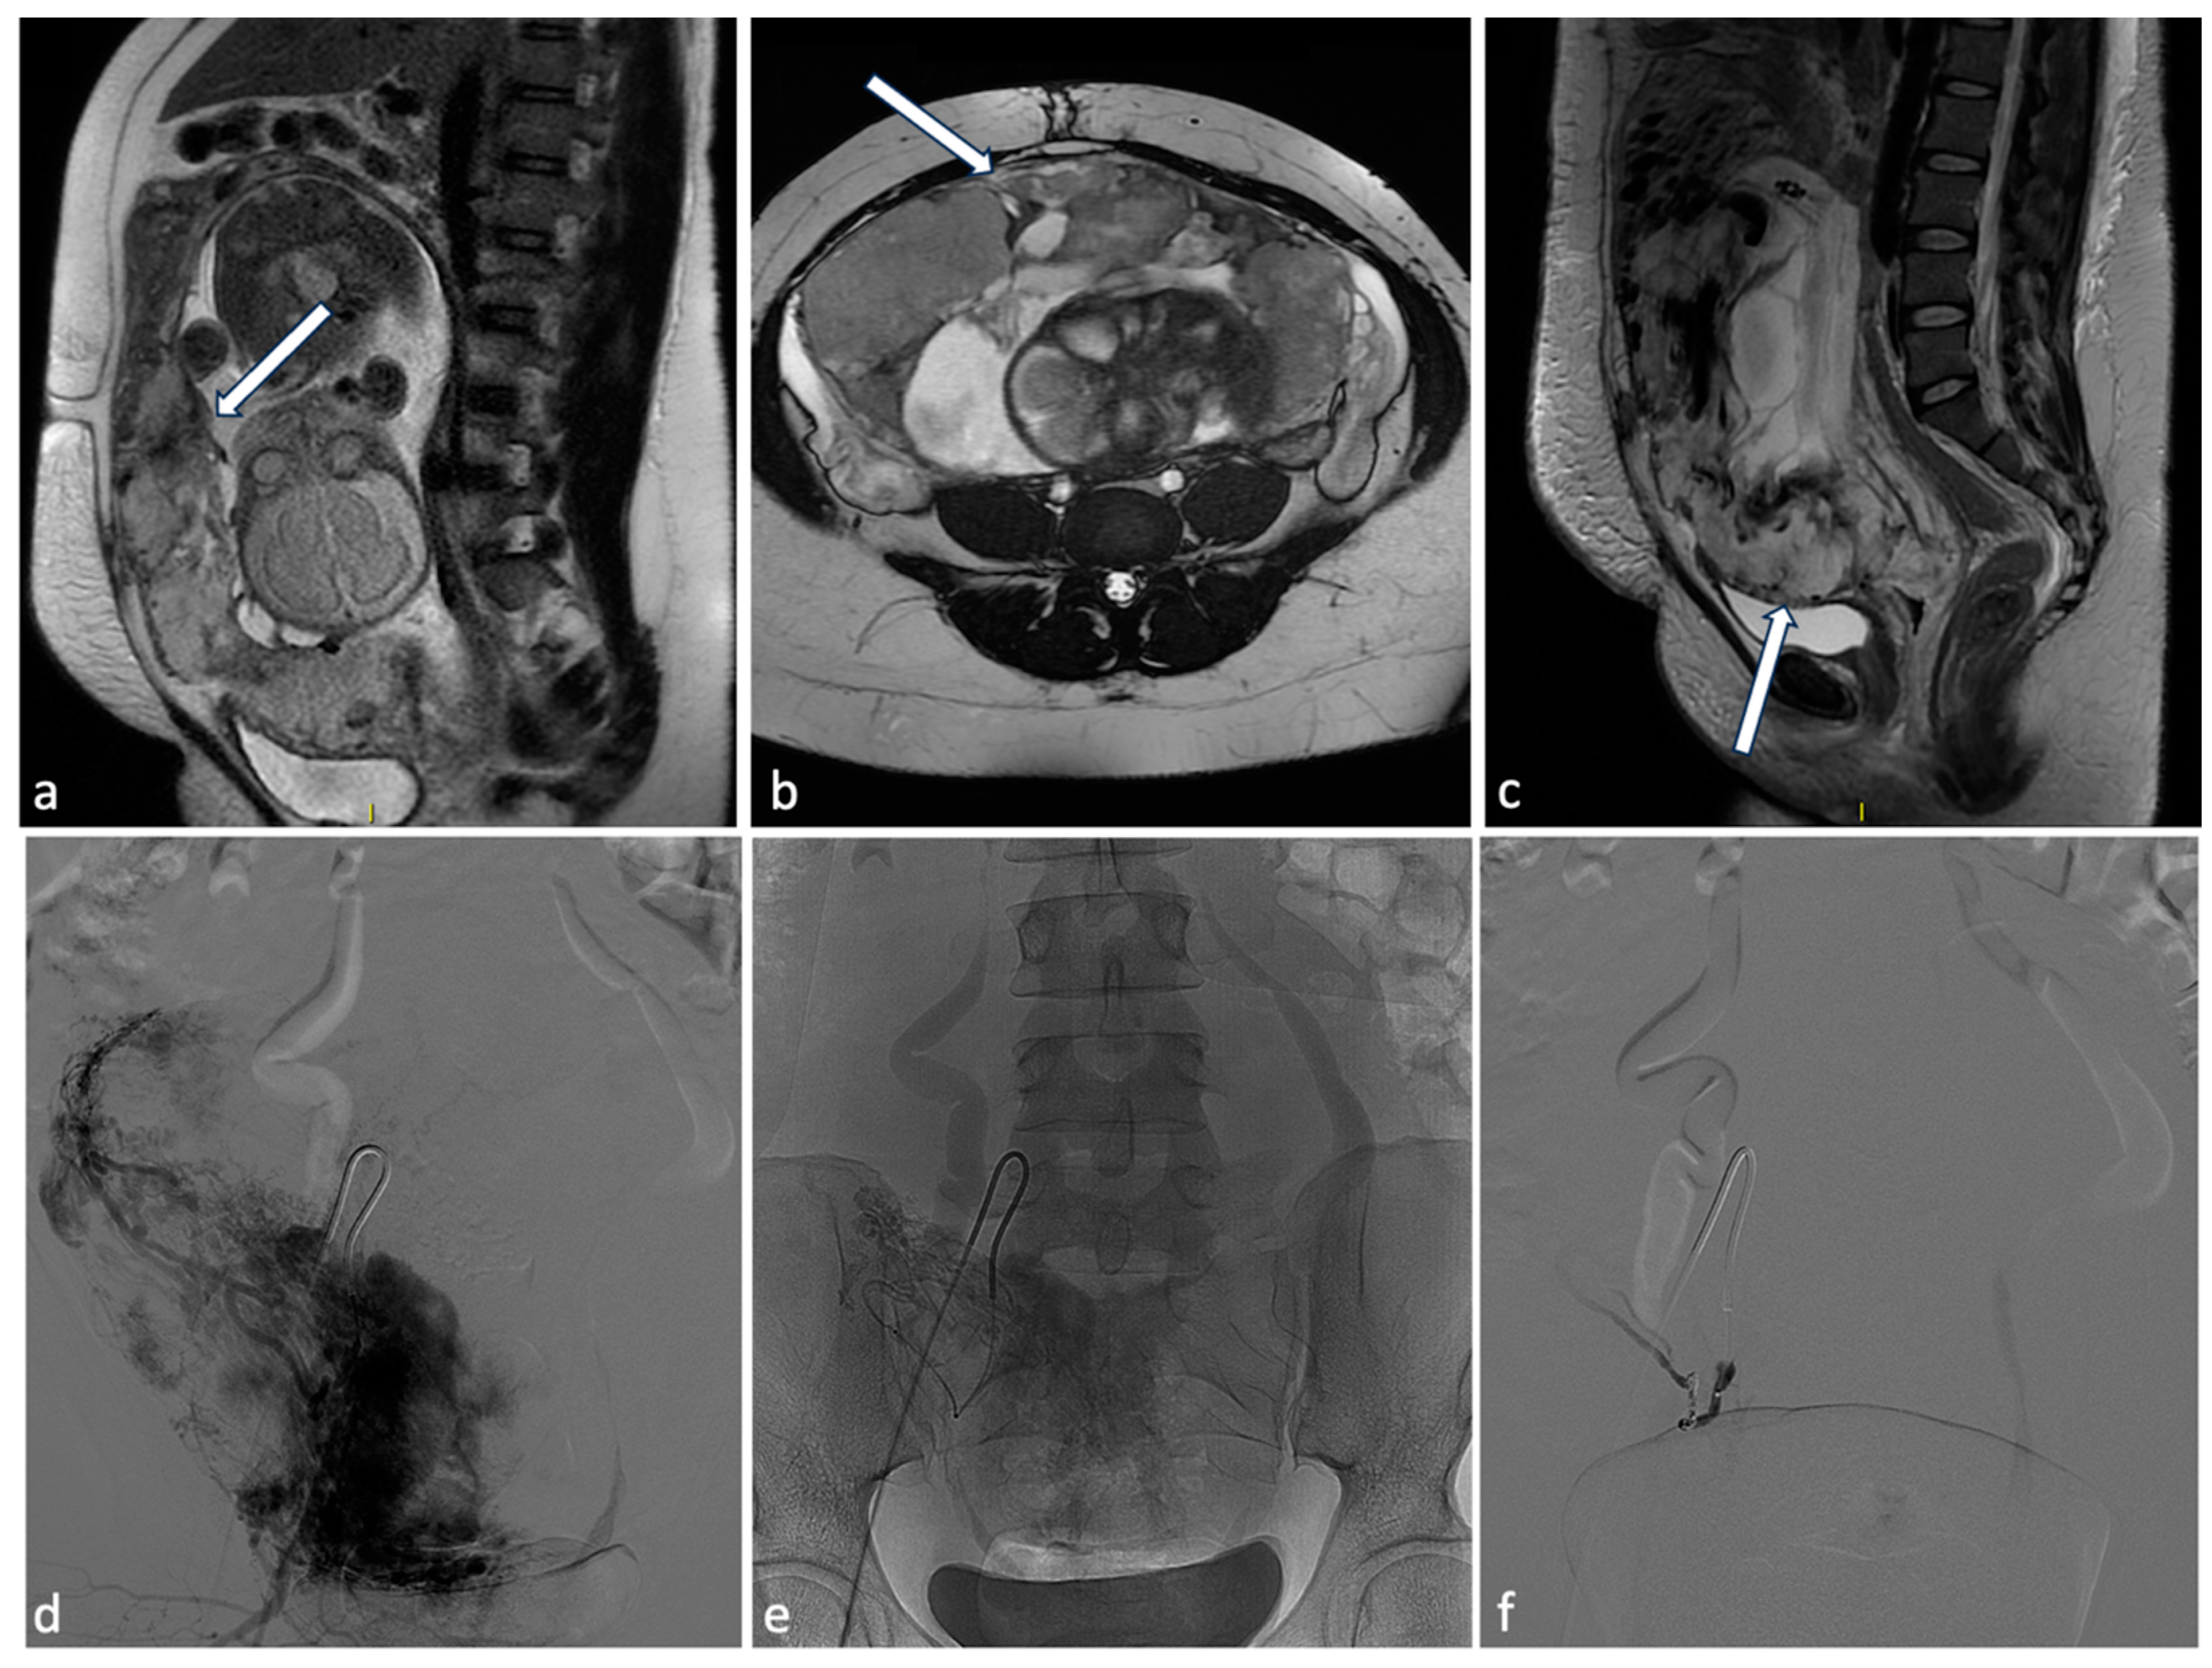

Figure 9.

Placenta percreta. A 38-year-old woman at 27 weeks of gestation with placenta previa percreta. Sagittal (a) and axial (b) T2W SSFSE images show a heterogeneous placental signal with some low signal intensity bands representing venous lakes (arrows). There is also a focal uterine bulge with thinning of the overlying myometrium. The patient underwent a caesarean section and extraction of the fetus but no secondment due to placenta percreta. In the post-partum MRI (c), signs of placental percreta were still present with an image of bladder infiltration (arrow), later confirmed at cystoscopy. It was decided to perform endovascular devascularization of the placenta percreta left in situ before proceeding to hysterectomy. Preliminary arteriography of the abdominal aorta documented hypertrophy of both uterine arteries, clearly greater on the right, which exuberantly vascularized the hypertrophied placenta, supplying multiple intraplacental high-flow vascular lakes (d). After superselective catheterization with a coaxial microcatheter of both uterine arteries and some of their distal branches, bilateral embolization was performed by infusion of a suspension of embolizing particles. The procedure was completed with release of 3 platinum microspirals (3 mm diameter) at the level of the distal right uterine artery (e), proximal to the origin of the main collaterals and 2 microspirals (3 mm) at the origin of the left uterine artery. At the end of the operation, satisfactory uterine and placental devascularization was shown (f).